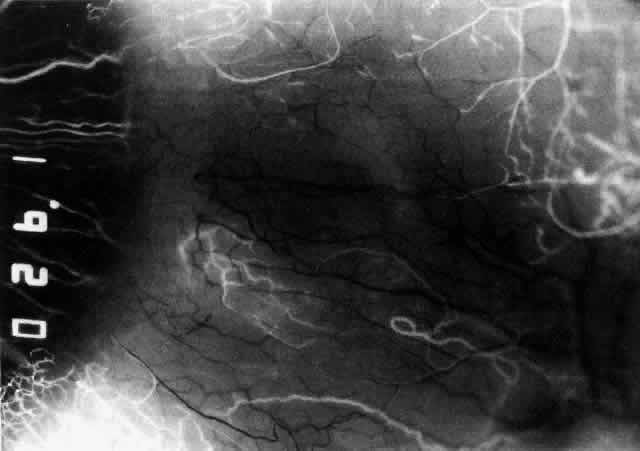

The characteristic features of necrotizing scleritis on fluorescein angiography are hypoperfusion and, eventually, nonperfusion of the vascular networks (Figs. 40 through 43).26 The initial changes are on the venous side of the capillary network; the transit time of the dye increases even if the eye is red and congested. If the disease process persists or has been present for a long time, thrombosis and permanent vaso-occlusive changes occur. These vessels (or the occluded capillary network) are bypassed by the opening of anastomotic channels. New vessels in a granuloma give rise to deep intrascleral leakage of dye (see Fig. 43). Conjunctival and episcleral involvement by the destructive change is late but is always preceded by vaso-occlusive changes that can sometimes be detected with use of the red-free light on the slit lamp (Figs. 44 and 45).